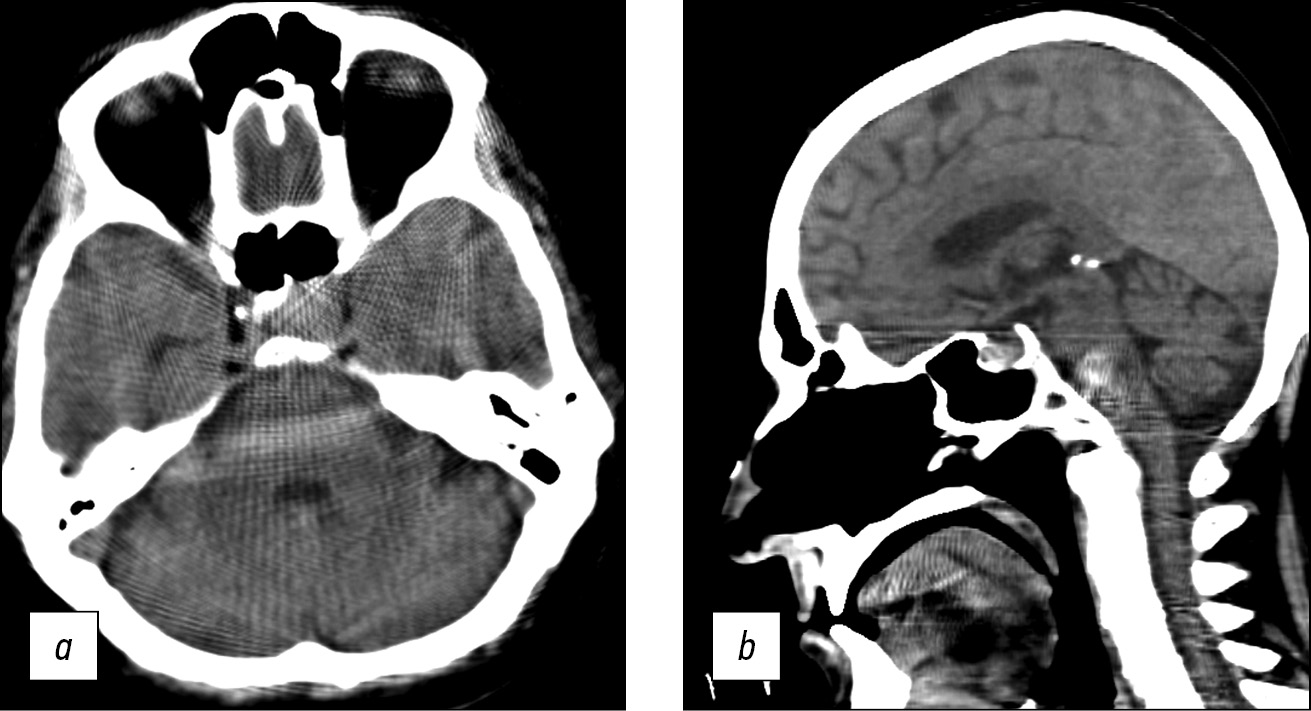

Brain CT was used to diagnose acute cerebrovascular accident, intracranial hematomas, brain tumors, and traumatic skull injuries (Fig. 7).

Fig. 7. Axial computed tomographic images of the brain: (a) reconstruction of a 3-mm low-density area at the anterior horn of the left lateral ventricle, in the periventricular, subcortical direction (CT image of subacute cerebrovascular accident of the left middle cerebral artery), and (b) a 1-mm site of subarachnoid hemorrhage with blood breakthrough into the ventricular system (vicarious hydrocephalus).

Windmill artifacts (Fig. 8a) were mixed with strike artifacts and helical scanning [5], and artifacts intensified at the level of skull base, where significant beam hardening and scattering artifacts occurred (Fig. 8, b). Therefore, subtentorial brain areas were challenging to assess.

Fig. 8. Axial (a) and sagittal (b) computed tomographic images of the head in the region of the posterior cranial fossa and base of skull showed windmill, strike, beam hardening, and scattering artifacts. Area of bone structures and the posterior fossa is hard to evaluate.